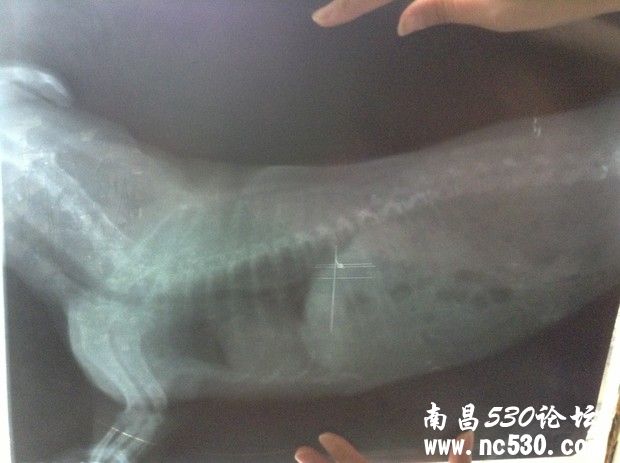

狗狗咳嗽已好几个月,之前一直是偶尔一两声卡卡干咳声,到最近转变成一连串咳嗽,明显加重,而且咳嗽声音变化了。前天带去医院看,打了X光,查了血常规和电解质(这个查没查我不知道医生也没说但收了费)。然后医生说心脏有点点肥大,应该是心脏顶到气管造成的咳嗽。别的血常规这些都正常,血压也正常。就说以后给它吃皇家心脏处方狗粮,然后开了几颗扩张支气管的药(肺心康),两三天的量。就这样了。但是狗狗回来还是一直咳,特别是晚上,咳得很可怜,咳到最后还象卡痰那样的象有痰吐不出来似的。我就是想知道,我家狗狗到底是不是因为心脏原因引起的咳嗽,还是会是别的?难道就让它这么咳下去么?皇家心脏处方狗粮现在买不到,还是吃的平常的,因为说它有点点偏胖就给它吃得很少减了量。它现在饿跑来想吃我都不敢给它吃,请问这样让它少吃的做法对么?还是吃一般的狗粮可以么?

还有就是今天回来仔细看片子,发现下图那块(喉咙还是气管那下面我圈起来的地方)有块东西,也不知道是片子是脏的还是它身上的?特意放上来请各位专家医生看看。说实话,那天医生也没和我讲清楚,连查血那些的单子也没给我,病历也未给写,片子我还是走的时候要求要的。